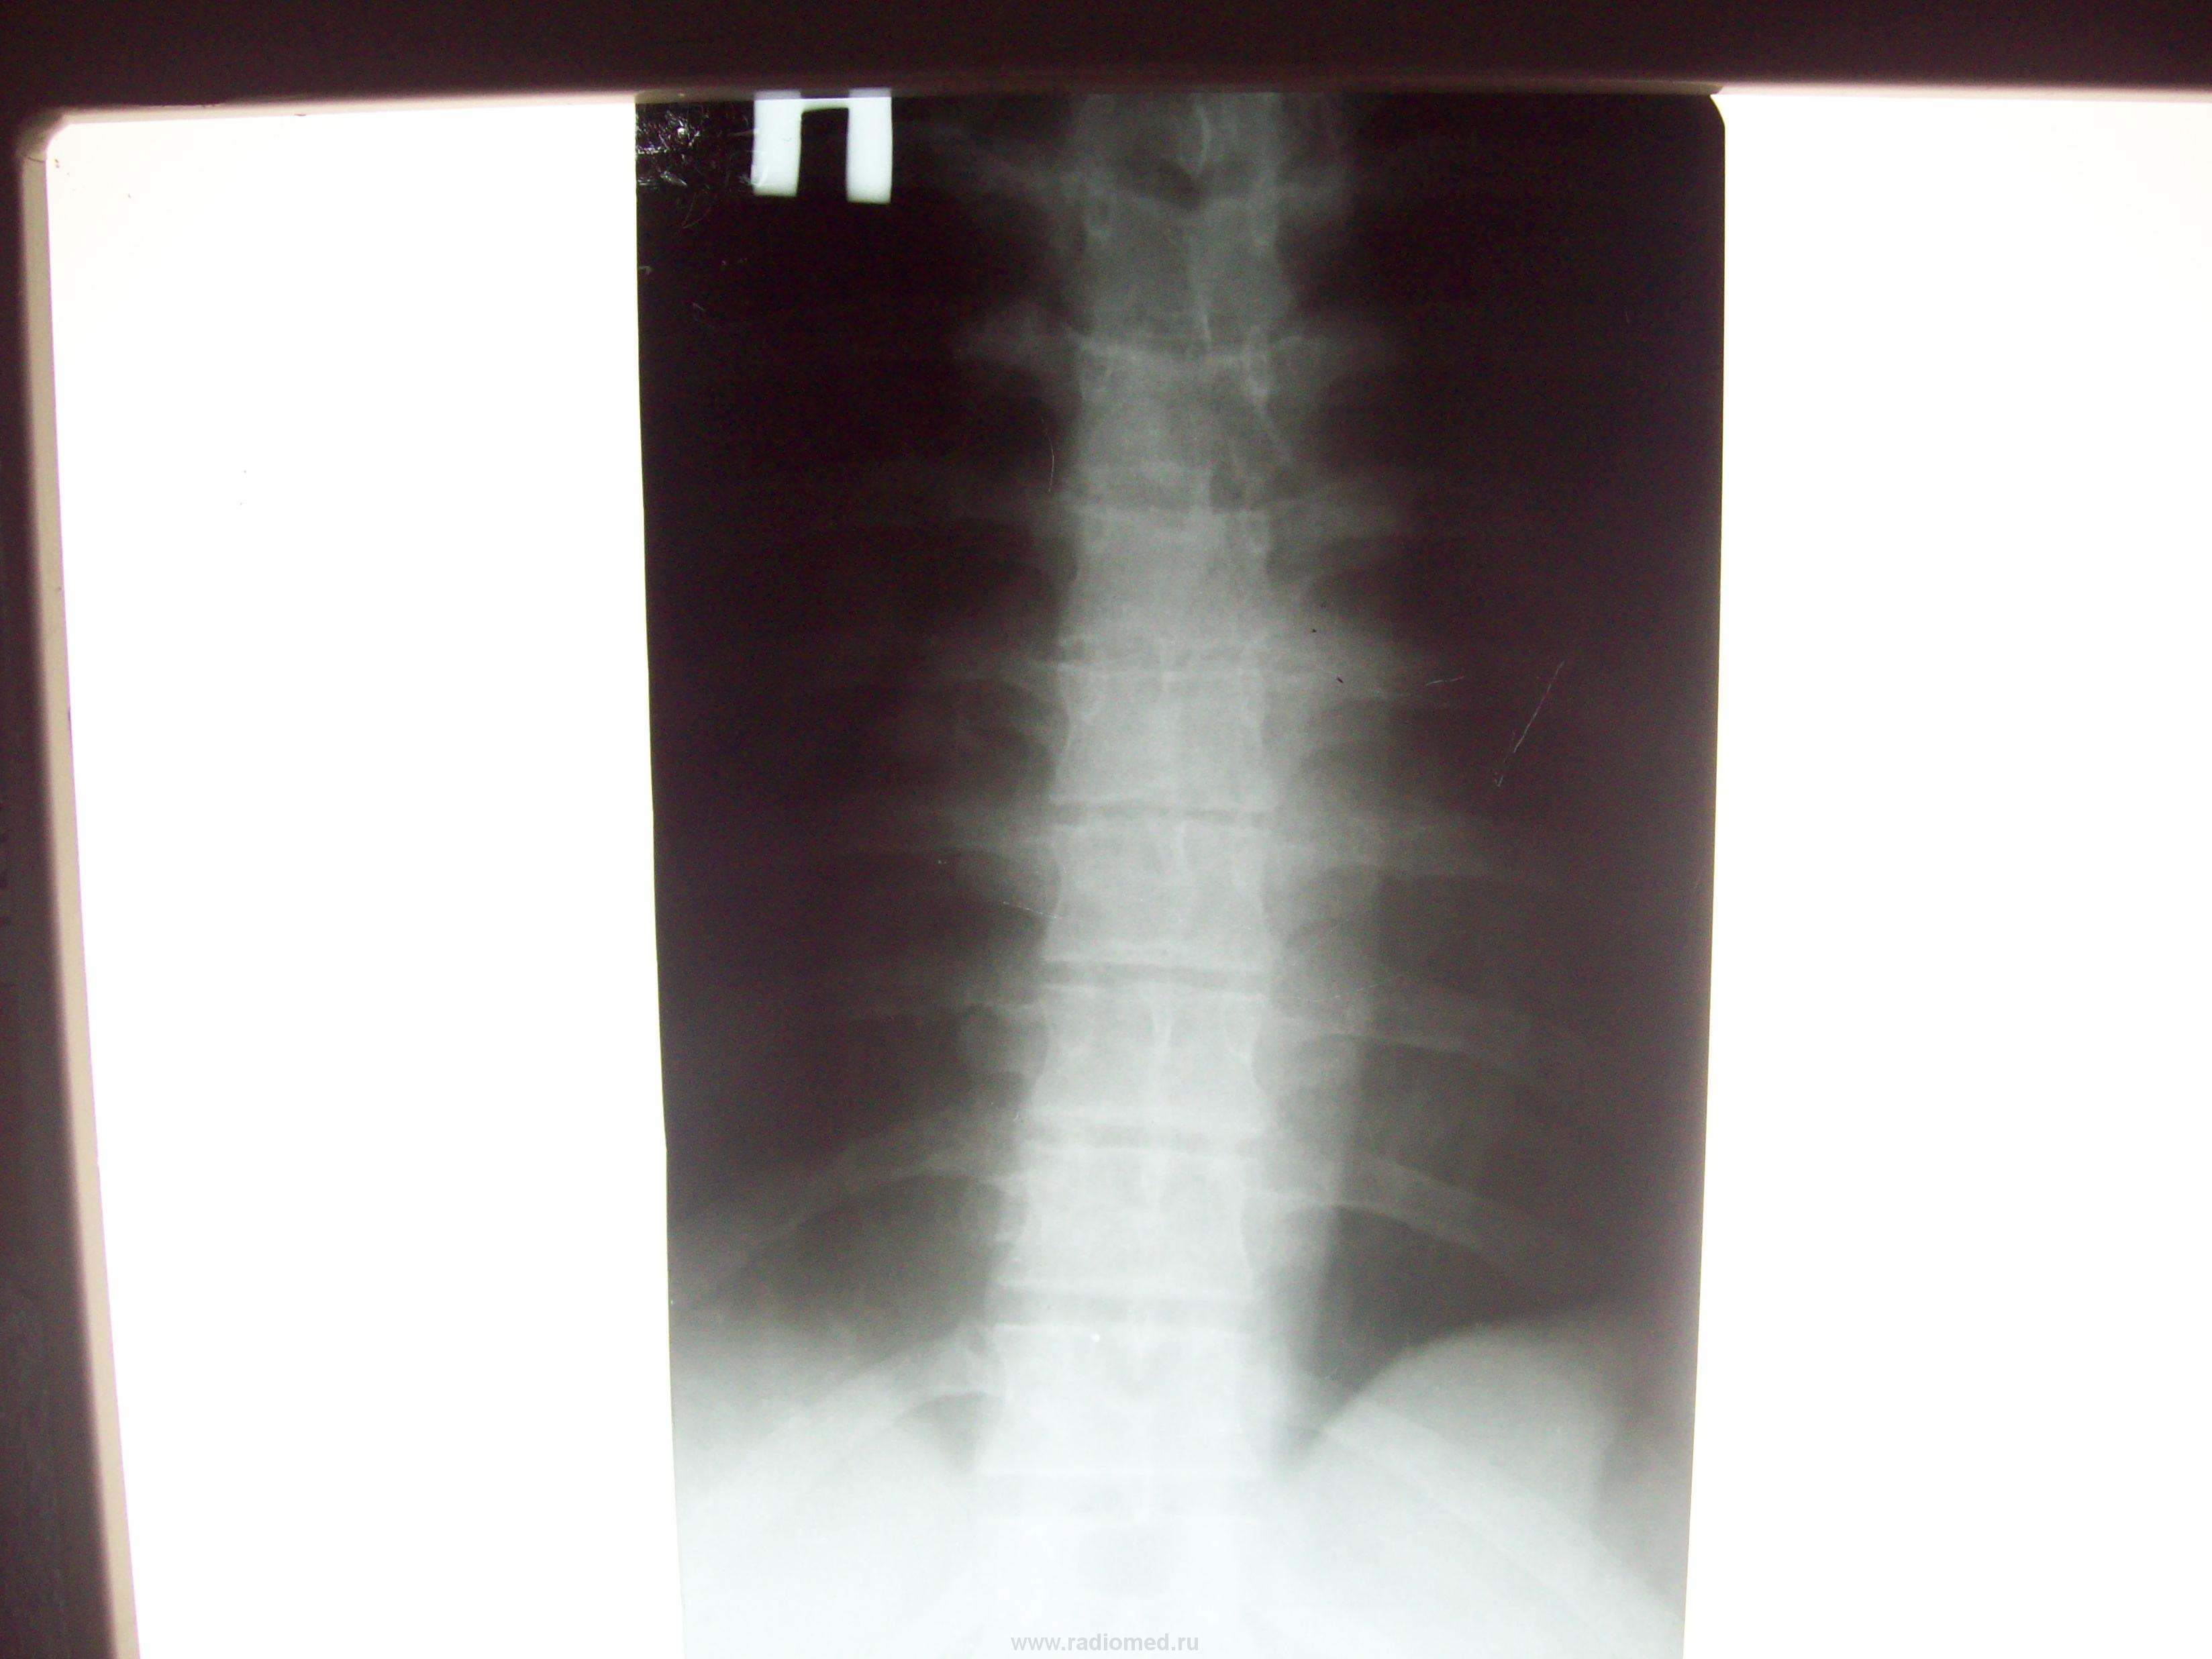

Пол пациента: Мужской пол Тип патологии: Воспалительное заболевание неинфекционной природы Область исследования: Скелетно-мышечная система Методы исследования: Rg Болеет с 16 мая 20010. Боли в грудном отделе позвоночника внезапно в проекции Т4-5. Подскажите! https://radiomed.ru/sites/default/files/styles/case_slider_image/public/user/2860/101_1861.jpg?itok=g2Ocd1JF https://radiomed.ru/sites/default/files/styles/case_slider_image/public/user/2860/101_1862.jpg?itok=NFv6FgD6 ID:3917 Чт, 20/05/2010 - 14:13 #1 Игорь Давыдов Не на сайте Был на сайте: 15 лет 8 месяцев назад Зарегистрирован: 13.05.2010 - 00:40 Публикации: 10 Упорно старался что-либо разглядеть, не вышло, по существу сказать что либо затрудняюсь :( может быть порекомендовать КТ на этом же уровне? Чт, 20/05/2010 - 15:25 #2 Vikkur Не на сайте Был на сайте: 4 года 9 месяцев назад Зарегистрирован: 24.09.2009 - 14:34 Публикации: 1749 Вот мне видиться, что Th9,10 задействованы.Приложения: Виктор. Чт, 20/05/2010 - 21:50 #3 Грицько Виталий Не на сайте Был на сайте: 9 лет 1 месяц назад Зарегистрирован: 05.01.2010 - 14:06 Публикации: 1058 Уважаемый коллега, если есть возможность попробуйте переснять, может интересующими вас фрагментами получится. Сб, 22/05/2010 - 01:48 #4 ughnaya stolitsa Не на сайте Был на сайте: 14 лет 5 месяцев назад Зарегистрирован: 14.05.2010 - 19:25 Публикации: 28 Похоже на снижение высоты тела Th9, увеличение его горизонтального размера. Патол. перелом? Реком. прицельные R-граммы нижнегрудного отдела Сб, 22/05/2010 - 11:15 #5 Грицько Виталий Не на сайте Был на сайте: 9 лет 1 месяц назад Зарегистрирован: 05.01.2010 - 14:06 Публикации: 1058 ughnaya stolitsa wrote: Похоже на снижение высоты тела Th9, увеличение его горизонтального размера. Патол. перелом? Реком. прицельные R-граммы нижнегрудного отдела По боку полностью с вами согласен,но структуру рассмотреть не могу. Переснять данную область и добавить томограммы. Сб, 22/05/2010 - 12:22 #6 Катенёв Валенти... Не на сайте Был на сайте: 7 лет 2 месяцев назад Зарегистрирован: 22.03.2008 - 22:15 Публикации: 54876 Соглашусь с Виталием Орестовичем, что, по всей видимости, линейная томография даст дополнительную информацию или позволит поставить точку. Приложения:

Вот мне видиться, что Th9,10 задействованы.

Похоже на снижение высоты тела Th9, увеличение его горизонтального размера. Патол. перелом? Реком. прицельные R-граммы нижнегрудного отдела

Соглашусь с Виталием Орестовичем, что, по всей видимости, линейная томография даст дополнительную информацию или позволит поставить точку.